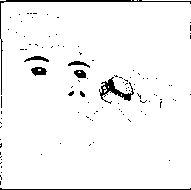

duymalısınız. Eğer bu vızıldama sesini duymazsanız, kapsül bölmesini açınız ve kapsülün, kapsül bölmesinde sıkışıp sıkışmadığını kontrol ediniz. Daha sonra 7. basamağı tekrarlayınız. Kapsülü sıkıştığı yerden kurtarmak için düğmelere tekrar BASMAYINIZ.

8. Cihazın içerisinden nefes aldıktan sonra, nefesinizi olabildiğince tutunuz ve cihazı ağızdan çıkarınız. Sonra burnunuzdan nefes veriniz. Kapsül bölmesini açınız ve kapsülde toz kalıp kalmadığını kontrol ediniz. Eğer kalmış ise 6-8. işlemleri tekrarlayınız

9. Tüm tozu kullandıktan sonra kapsül bölmesini açınız (Bkz. basamak 2). Boş kapsülü çıkarınız ve içeride kalan tozları temizlemek için kuru bir kağıt mendil ya da yumuşak bir fırça kullanınız.

Not: İnhalasyon cihazını temizlemek için SU KULLANMAYINIZ.

10. Önce ağızlığı, ardından kapağı kapatınız.

İlacınızı kullandıktan sonra ağzınızı suyla iyice çalkalayınız ve bu suyu tükürünüz. Bu işlem ağzınızda bir mantar enfeksiyonu (pamukçuk) gelişme olasılığını azaltacaktır.Değişik yaş grupları